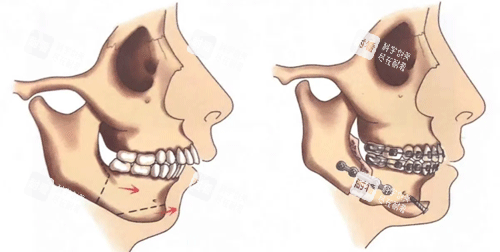

正颌手术则是通过移动、调整颌骨的位置来矫正牙颌面畸形。它可以针对上颌骨、下颌骨或者上下颌骨同时进行调整,但与双鄂手术不同的是,正颌手术更侧重于解决牙齿咬合不正以及颌骨位置不协调所导致的问题。手术的原理是通过切开颌骨,将其移动到合适的位置,然后用钛板等固定材料进行固定,使牙齿能够正常咬合,面部形态也得到相应的改善。

手术操作:手术同样在全身麻醉下进行。根据手术方案,医生会对相应的颌骨进行截骨和移动。如果是上颌骨手术,可能会通过口腔内切口进行;如果是下颌骨手术,可能需要在口腔外或口腔内联合切口。手术时间相对双鄂手术较短,一般在2 - 4个小时左右。